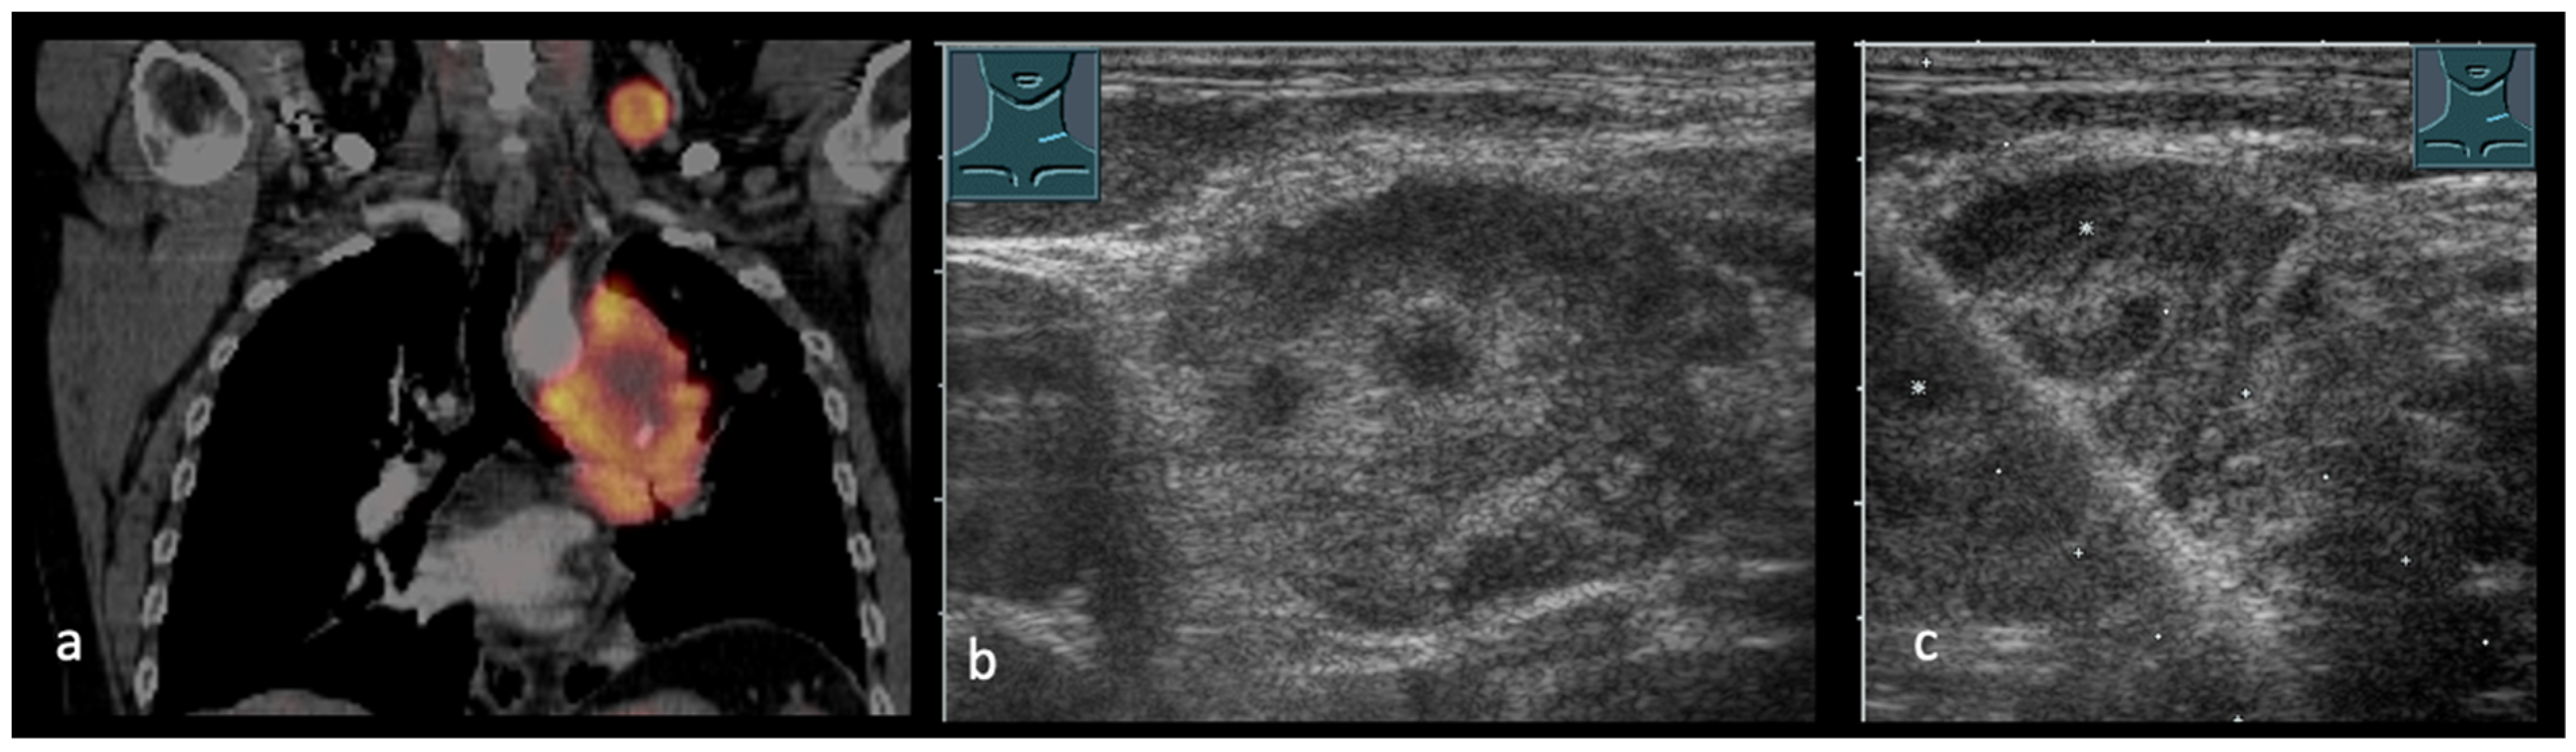

2. Transcutaneous Ultrasound in the Primary Staging of Lung Cancer

3. Transthoracic Ultrasound in the Evaluation and Characterizing of Local Tumor Size (T-Stage)

- Findeisen, H.; Trenker, C.; Figiel, J.; Greene, B.H.; Görg, K.; Görg, C. Vascularization of Primary, Peripheral Lung Carcinoma in CEUS—A Retrospective Study (n = 89 Patients). Ultraschall Med. 2019, 40, 603–608. (In English) [Google Scholar] [CrossRef] [PubMed]

- Safai Zadeh, E.; Huber, K.P.; Görg, C.; Prosch, H.; Findeisen, H. The Value of Contrast-Enhanced Ultrasound (CEUS) in the Evaluation of Central Lung Cancer with Obstructive Atelectasis. Diagnostics 2024, 14, 1051. [Google Scholar] [CrossRef]